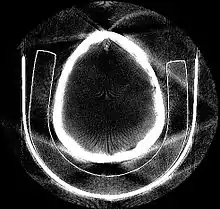

The projection of an object, resulting from the tomographic measurement process at a given angle , is made up of a set of line integrals (see Fig. 1). A set of many such projections under different angles organized in 2D is called sinogram (see Fig. 3). In X-ray CT, the line integral represents the total attenuation of the beam of x-rays as it travels in a straight line through the object. As mentioned above, the resulting image is a 2D (or 3D) model of the attenuation coefficient. That is, we wish to find the image . The simplest and easiest way to visualise the method of scanning is the system of parallel projection, as used in the first scanners. For this discussion we consider the data to be collected as a series of parallel rays, at position , across a projection at angle . This is repeated for various angles. Attenuation occurs exponentially in tissue:

Deep learning methods are widely applied to image reconstruction nowadays and have achieved impressive results in various image reconstruction tasks, including low-dose denoising, sparse-view reconstruction, limited angle tomography and metal artifact reduction. An excellent overview can be found in the special issue [5] of IEEE Transaction on Medical Imaging. One group of deep learning reconstruction algorithms apply post-processing neural networks to achieve image-to-image reconstruction, where input images are reconstructed by conventional reconstruction methods. Artifact reduction using the U-Net in limited angle tomography is such an example application.[6] However, incorrect structures may occur in an image reconstructed by such a completely data-driven method,[7] as displayed in the figure. Therefore, integration of known operators into the architecture design of neural networks appears beneficial, as described in the concept of precision learning.[8] For example, direct image reconstruction from projection data can be learnt from the framework of filtered back-projection.[9] Another example is to build neural networks by unrolling iterative reconstruction algorithms.[10] Except for precision learning, using conventional reconstruction methods with deep learning reconstruction prior [11] is also an alternative approach to improve the image quality of deep learning reconstruction.